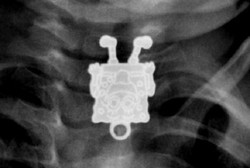

Ada 'SpongeBob' Terjebak di Kerongkongan Balita Ini

Wajar kiranya bila anak usia 1-3 tahun memasukkan sesuatu ke dalam mulutnya karena itu tandanya ia sedang mengeksplor sesuatu. Namun kadangkala benda-benda ini justru dan terjebak di dalam tubuh si kecil.